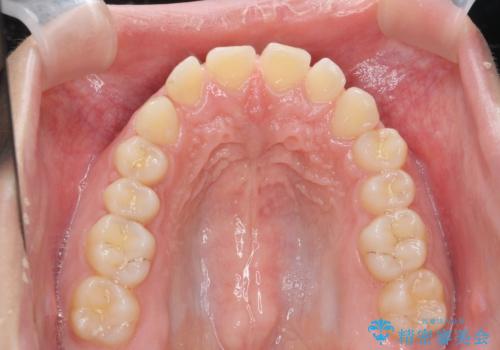

深い噛み合わせ、すきっ歯の改善 ワイヤーを用いたマルチブラケット矯正

- 噛み合わせが深く、前歯が突き出て隙間が出てきたことの改善を希望され矯正治療の相談で当院に初診来院されました。

ワイヤーを用いたマルチブラケット矯正を行うことで深い噛み合わせを改善し、前歯の隙間もなくし審美的な歯列へと治療をおこなっていきます。